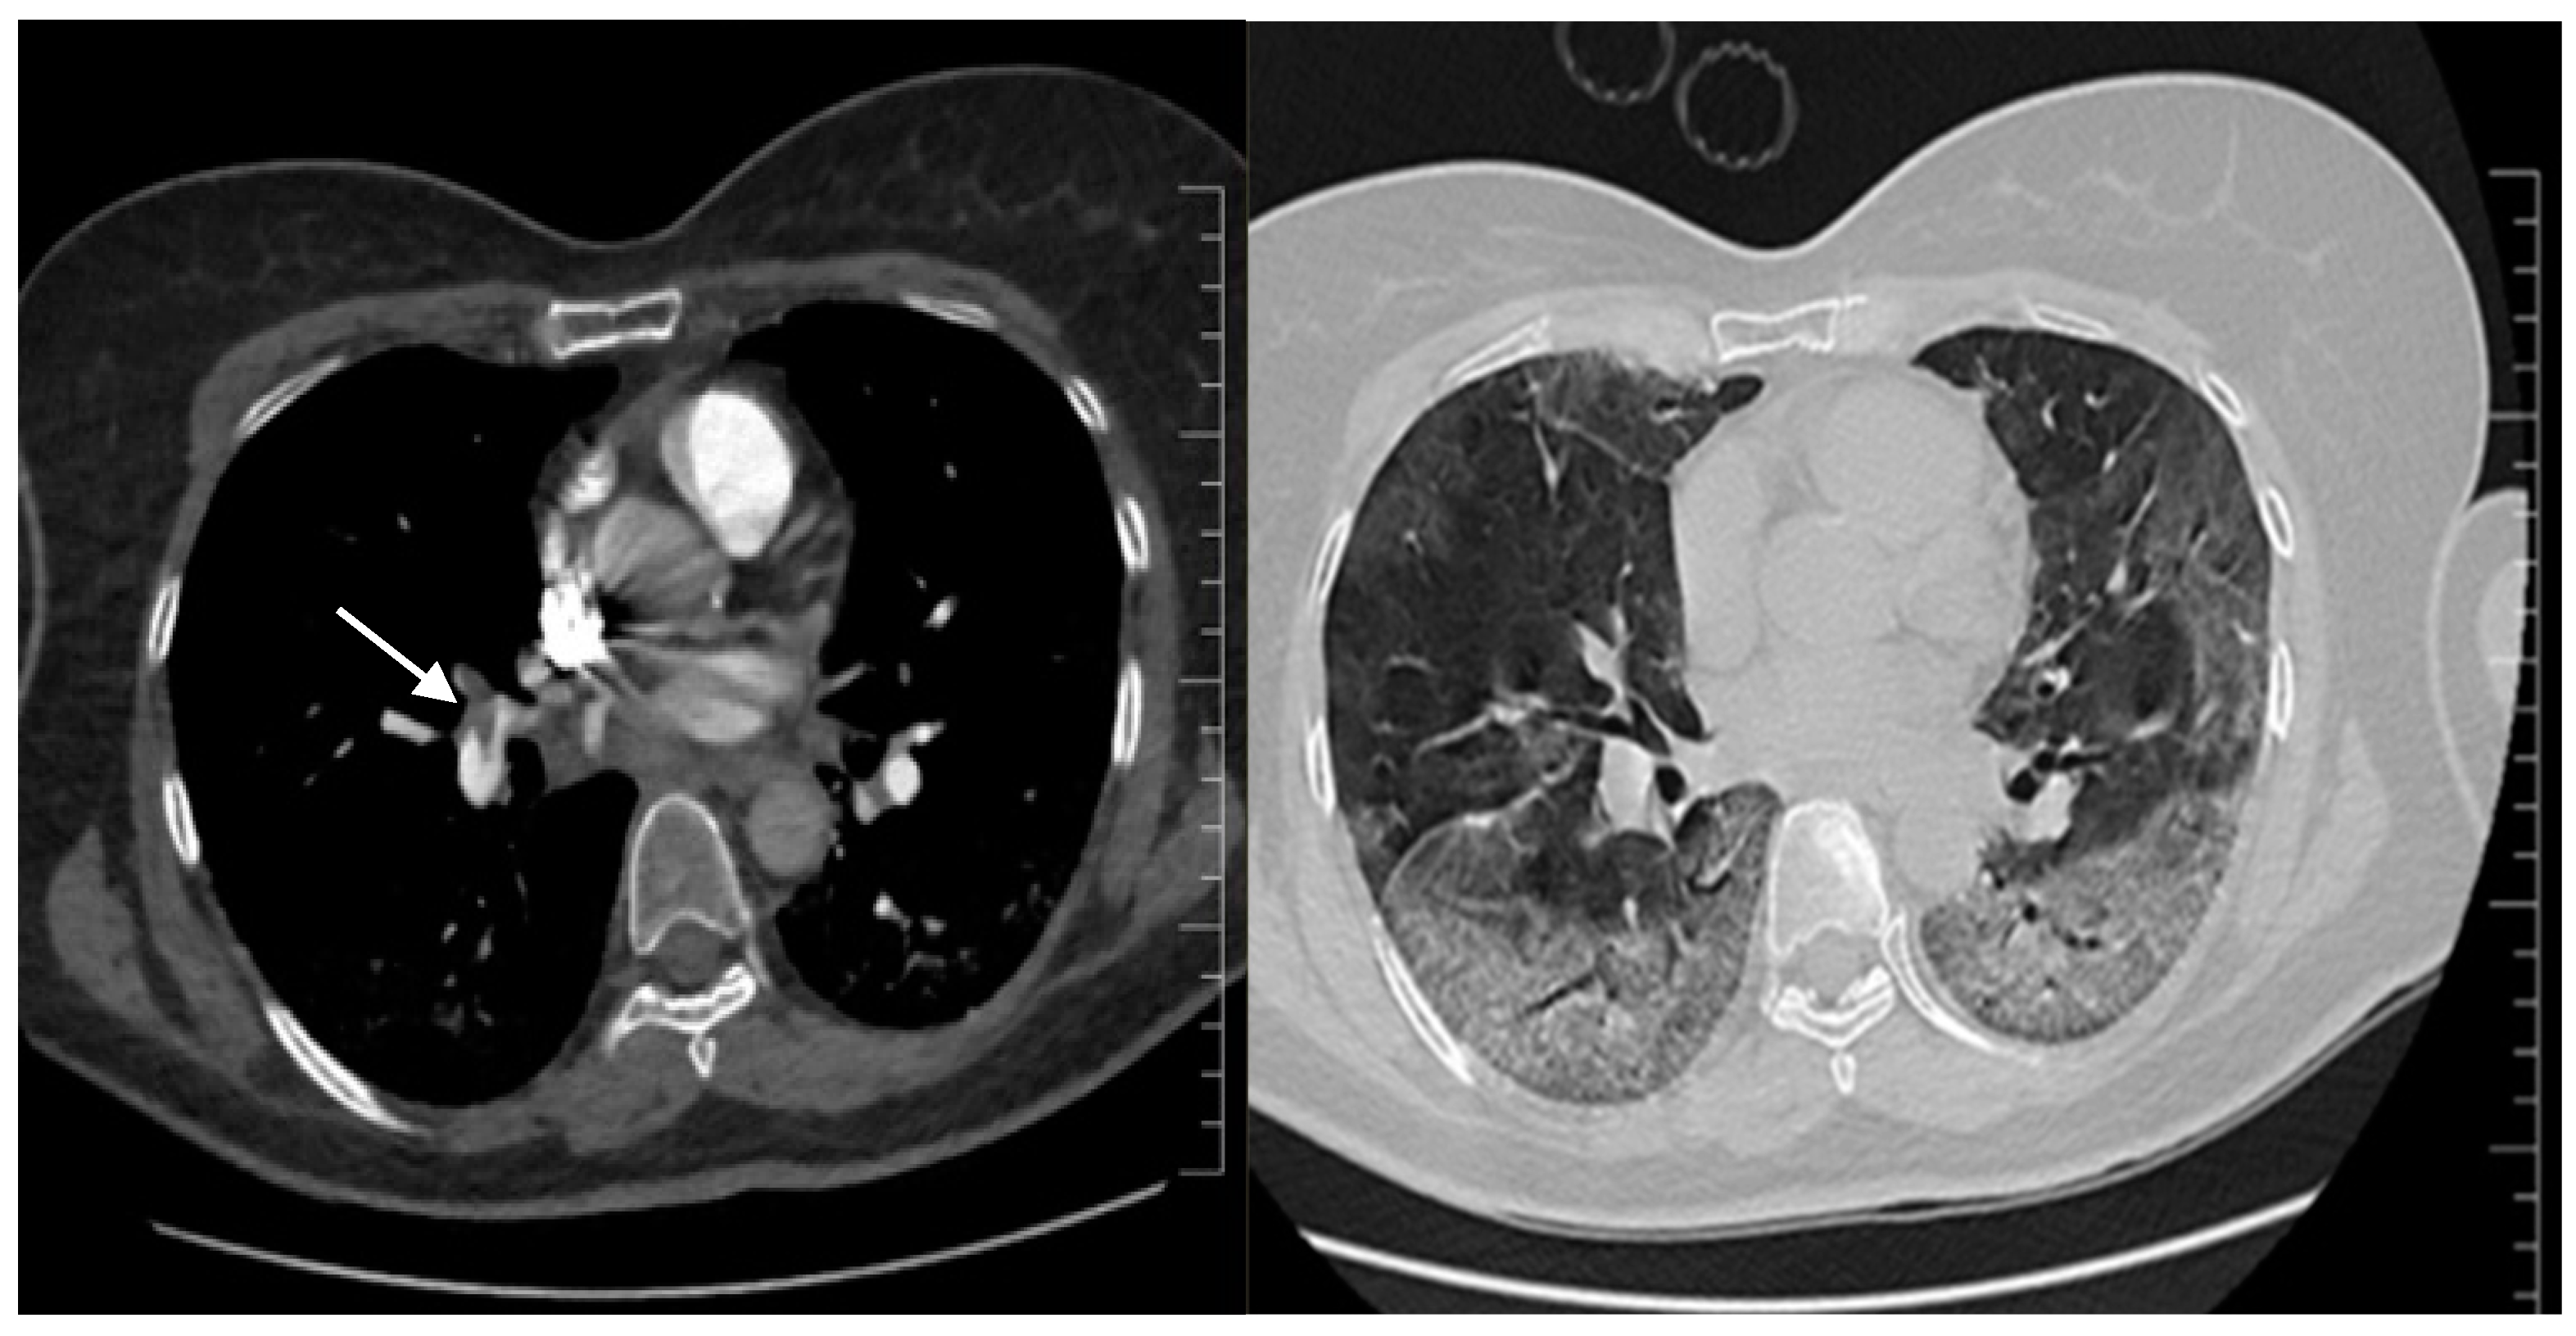

Septic shock with disseminated intravascular coagulation or a high-risk (massive) pulmonary thrombosis (PT) were considered. The SOFA score was 12 points. The patient received i.v. fluids, vasopressors and was switched from LMWH to unfractionated heparin (UFH). Extensive microbiological samples were collected, and broad-spectrum i.v. antibiotic and antifungal therapy were started. Remdesivir and Anakinra were stopped because of acute ischemic hepatitis. Echocardiography revealed paradoxical septal motion, right ventricular dilation with severe dysfunction, mild tricuspid regurgitation and a dilated inferior vena cava. A CT pulmonary angiogram (CTPA) confirmed the massive PT (Figure 1, left) and described a progression of COVID-19 pneumonia (60% of lung parenchyma) (Figure 1, right). No clinical or ultrasound imaging signs of deep venous thrombosis were found.

Figure 1. Second chest CT imaging, CT pulmonary angiography: on the left—main pulmonary right artery massive pulmonary embolism (arrow) and extending to the left pulmonary arteries; on the right—severe COVID-19 pneumonia, with lesions involving 60% of the lung parenchyma.